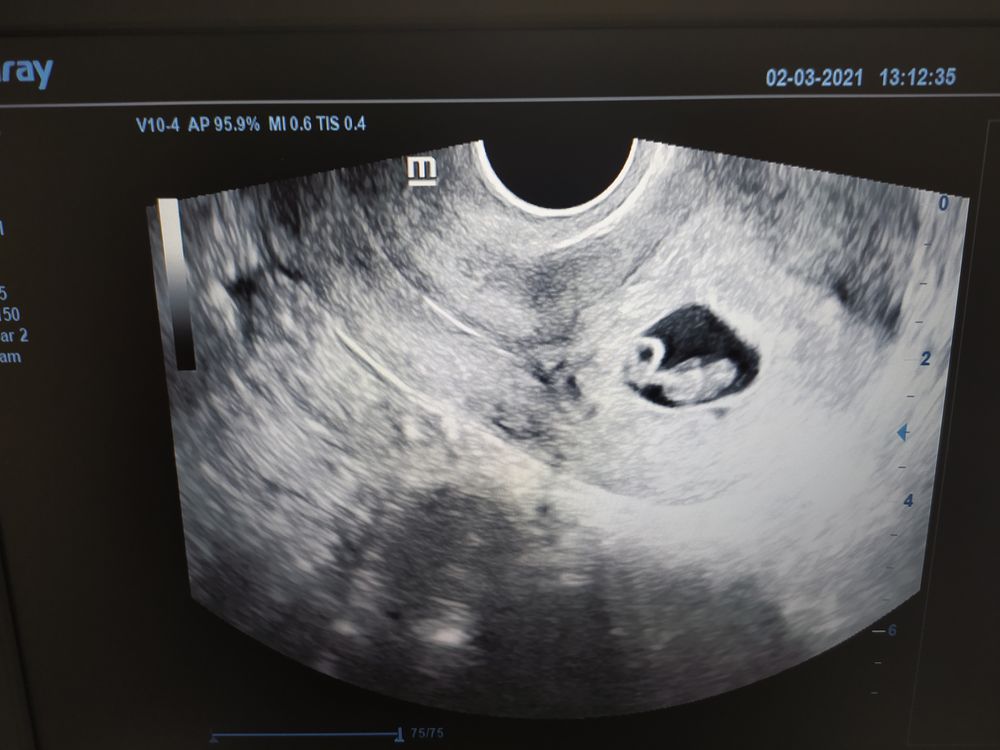

7 неделя внематочной

7 неделя внематочной 107 фото